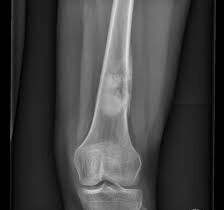

El osteosarcoma es el tipo más común de cáncer óseo primario y se caracteriza por la proliferación anormal de células óseas inmaduras. La clasificación por grados del osteosarcoma se basa…